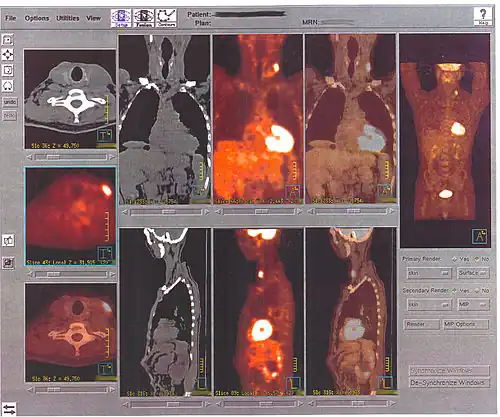

Une caméra TEP est un appareil qui a l’aspect d’un scanner mais son principe de fonctionnement est différent. En effet, l'atome radioactif (par exemple, le fluor 18) se désintègre en émettant un positon. Celui-ci va s'annihiler avec un électron du milieu, après un très court parcours de l'ordre du millimètre (0,6 mm dans l'eau pour le positon du 18F). Cette annihilation produit deux photons gamma de 511 keV qui partent sur une même direction mais dans un sens opposé, ce qui rend possible le traitement tomographique des données. En effet, les capteurs situés tout autour du patient détectent les photons d'annihilation en coïncidence (c’est-à-dire ceux qui arrivent en même temps), ce qui permet d'identifier la ligne sur laquelle se situe l'émission des photons. Un système informatique reconstitue ensuite à l'aide d'un algorithme de reconstruction les images de la répartition du traceur au niveau d’une partie ou de la totalité du corps sous la forme d'une image 2D ou d'un objet 3D. Les images ainsi obtenues sont dites « d’émission » (la radioactivité provient du traceur injecté au patient). La résolution spatiale de l'image ainsi obtenue est comprise entre 4 et 7 mm en imagerie clinique (pour l'homme) et inférieure à 1,5 mm en imagerie préclinique (destinée au rat ou à la souris)[7].

Il est possible d’améliorer la qualité des images en utilisant le principe de correction d’atténuation. Lors de la traversée du corps, de nombreux photons gamma subissent une atténuation liée aux structures traversées et à leur épaisseur. En effet, un foyer hyperfixant situé en profondeur sera moins visible qu'un même foyer situé en surface. Pour effectuer cette correction, on utilisait initialement des images de transmission obtenues grâce à une source radioactive qui tourne rapidement autour du patient. Cependant la plupart des caméras TEP sont aujourd'hui couplées à un tomodensitomètre à rayons X (système TEP/TDM ou PET/CT en anglais), ce qui permet de superposer l'image fonctionnelle (image TEP) à sa localisation anatomique précise dans le corps (image CT). La correction d’atténuation ainsi réalisée permet d'effectuer l'examen beaucoup plus rapidement et d'obtenir des images de meilleure qualité.

Toutes les informations recueillies par la caméra TEP reposent sur la radioactivité repérée dans les tissus après l'injection du 18F-FDG au patient. Le système informatique relié à la caméra TEP produit des images en coupe et en trois dimensions des endroits du corps où le 18F-FDG s'est accumulé.